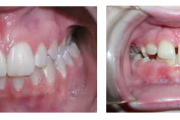

Ruumipuudus eesmiste hammaste osas

Normaalse jäävhammaskonna pilt küljelt ja eest vaadatuna.